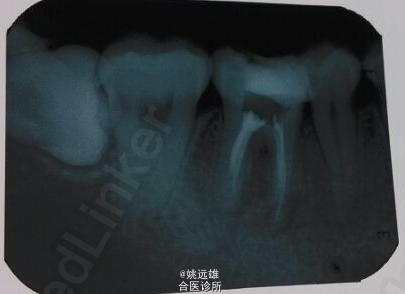

检查:36牙近中邻合面树脂充填体,探(-),冷(-),叩(++),无明显松动,唇颊侧未见明显瘘道。 x线片示36牙近中邻合面牙体组织高密度影像,髓腔内可见充填物,根尖周组织暗影。(初诊片患者丢失,未取得照片)

诊断:36牙慢性根尖周炎 治疗计划: 36牙根管治疗+树脂充填+冠修复 处置: 去除树脂充填物后常规根管扩挫,根测仪可测得根管长度,试尖,封药后预约复诊。(试尖片中远颊根疑似未到根尖孔,反复根测仪确认后长度不变,到工作长度) 复诊时常规根管充填。

3月后随访检查患者情况,无不适,遂建议行冠修复。 讨论:1、工作长度的确定:目前一般使用根测仪来确定工作长度,国内外的研究发现,根测仪测定的长度准确率较高,可以作为标准。 2、根尖孔的开口:根管的开口不一定是在根尖,也有可能在根尖区的侧壁,或者其它的位置,因此x线片中未到根尖的也未必是没到工作长度。